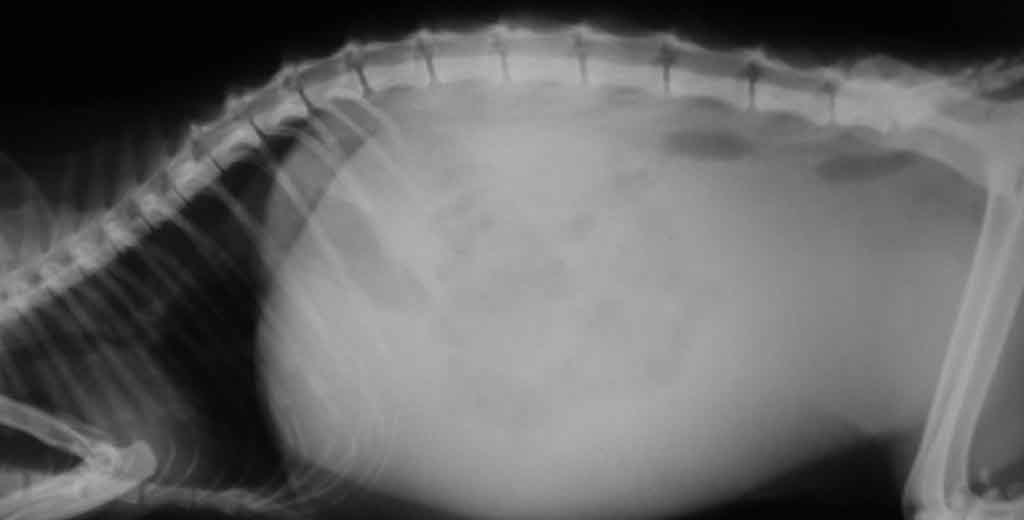

Симптоматика асцита

Наиболее типичный признак синдрома — увеличение живота в объеме. Симптомы раскрываются постепенно, в зависимости от скорости накопления вещества. При чрезмерном количестве транссудата брюшина становится большой и тугой.

Домашним тестом для определения асцита служит одна простая манипуляция. Кота следует поставить на задние лапы. Если живот стал похожим на грушу, с характерным для этого фрукта расширением в нижней части, нужно немедленно показать питомца ветеринару.

Главным проявлением асцита считается грушевидная форма живота животного в стоячем положении

По возвращении животного в исходное положение через несколько минут брюшко приобретает прежние очертания. Подобный эффект происходит в результате стекания жидкости вниз. У кошек с длинным подшерстком присущее асциту увеличение брюшины будет малозаметно. Симптоматика обусловлена степенью тяжести недуга и скоростью накопления транссудата.